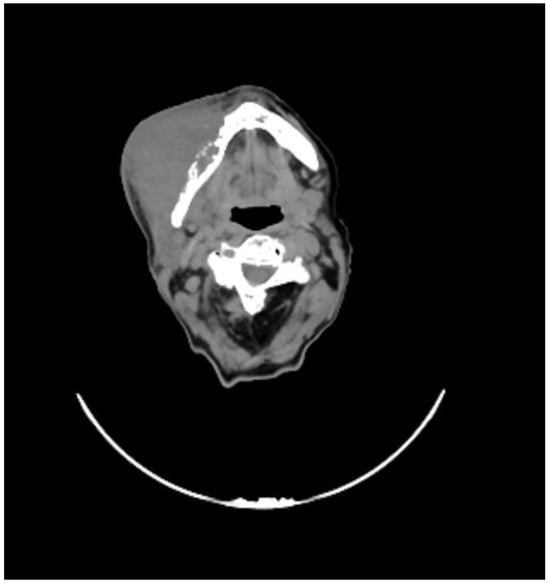

She underwent a maxillofacial computed tomography (CT) scan, which revealed a lesion of the right genial mucosa with infiltration of the skin, buccinator muscle, and the cortex of the mandibular bone, affecting the alveolar canal, and it also revealed the presence of necrotic, colliquative, and confluent lymphadenopathies (Figure 1).

Figure 1. CT performed before the start of therapy, showing the extent of disease with infiltration of the skin and mandible.